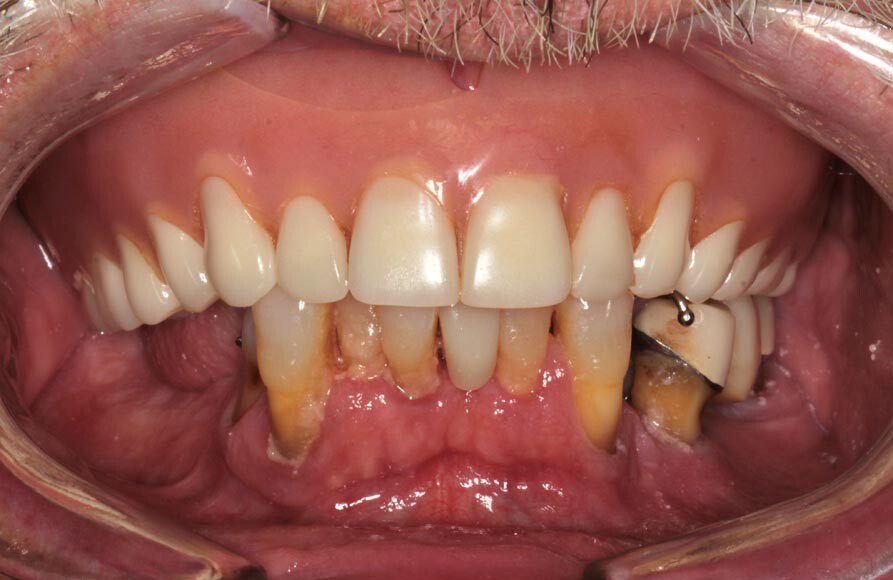

Frontal temporary smile. The patient heals for two additional months and returns to start the process for fabrication of the permanent implant bridges. We begin by assessing and photographing the temporary bridges. There are several issues with the first temporary bridges. Mainly, because he wore his original denture after the first surgery, we were unable to correct the left-to-right cant (slant) until now.